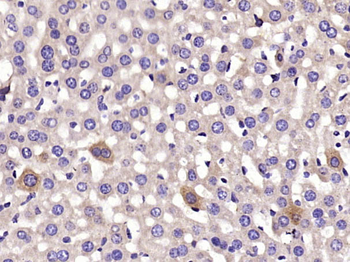

IF, IHC-Fr, IHC-P, WB

应用稀释比例:WB=1:500-2000, IHC-P=1:200-800, IHC-F=1:50-200, IF=1:50-200